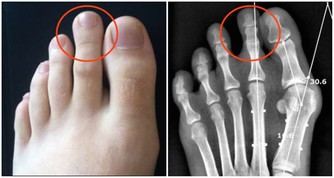

進而形成尿酸鹽結晶,沉積在關節內,造成關節疼痛及腫脹。

圖片翻攝自谷歌,下同。